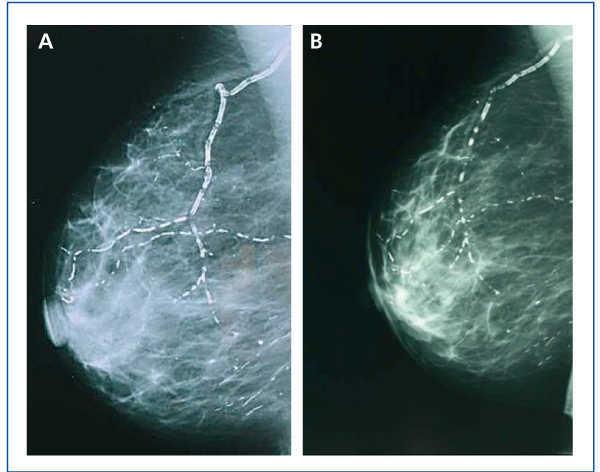

Calcification of the mammary artery detected in the mammography is proof of generalised atherosclerotic vascular disease (ASVD), in both general population and diabetic patients. A mammography is a highly sensitive diagnosis technique for calcification characterisation, including VC; furthermore, it may be a potentially useful tool for diagnosing VC in CKD women.8

In January 2006, she presented serious SPTH, with notable increase in iPTH levels. The parathyroid ultrasound revealed an echo-rich pseudo-nodular structure in the posteriomedial area of the left thyroid lobe, compatible with parathyroid gland hypertrophy. A series of X-rays showed signs of hyperparathyroidism in the bones of both hands and wrists, with VC in radial and interdigital arteries. The mammography revealed multiple linear VC in both breasts (Figures: 1A, 2A, 3A and 4A; hand and mammary gland images in 2006).

During this period, the X-ray series showed that the interdigital artery calcifications had disappeared, and the bone appeared better structured (Figures 1B and 2B; hand X-ray, 2007). The mammography also showed regression of the VC. Initial linear calcifications were replaced by irregular calcifications (Figures 3B and 4B; mammary glands in 2007).

Regression is evident in the mammographies, where we see how linear calcification was replaced by smaller areas of patchy irregular calcification. The images show how clearly VC can be seen in the mammographies, enabling accurate follow-up of their evolution. This is therefore a useful economic and accessible technique for VC diagnosis and follow-up in women with CKD.8,27 The presence of VC in a mammography is considered a cardiovascular risk marker in the general population, which is related to atherosclerosis and diabetes mellitus. However, for the uraemic population, a recently published study establishes the existence of histological correlation between CV presence in a mammography and calcification of the medial layer in arteries.28 Whereas calcification on the arterial intima is essentially related to atheromatosis and inflammation, medial artery calcification has a greater relation to CKD and associated metabolic disorders.5 In this case, given that it is a young woman without additional cardiovascular risks, one might consider that the calcification present in the mammary glands was more related to CKD and mainly affected the medial layer. Were this the case, regression of the mammary calcifications observed could be justified by the correct control of MBD-CKD disorders, since this regression would be unlikely in other patients in whom the VC at the arterial intima and media layers converge due to the interaction of many other factors, thus making the desired regression difficult to achieve.

Figure 3. (A) Anteroposterior X-ray of mammary gland in 2006. (B) Anteroposterior X-ray of mammary gland in 2007

Figure 4. (A) Craniocaudal breast X-ray in 2006. (B) Craniocaudal breast X-ray in 2007